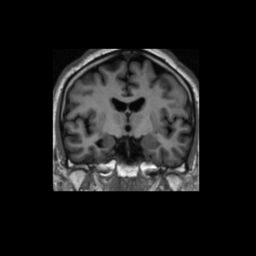

Test/Retest Reliability

FSL was run on each scan in the Brain Segmentation Testing Protocol (BSTP) between-scanner test/retest dataset. Select a subject below to see volumes for each subject across the subject's scans.